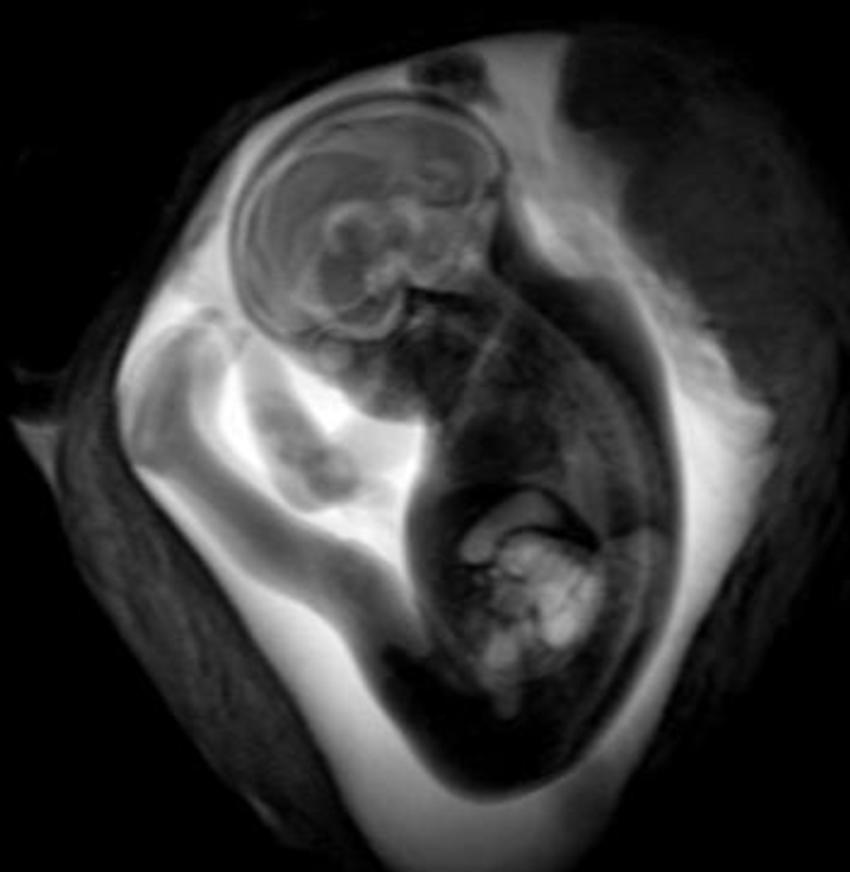

Figure 2. Image of fetus.

Dr. Stöcklein and colleagues used fetal MRI to study 33 patients with COVID-19 infection during pregnancy. The patients were roughly 28 weeks into their pregnancies, on average, with symptom onset occurring at a mean of just over 18 weeks into the pregnancy. The most common maternal symptoms were loss or a reduced sense of smell and taste, dry cough, fever and shortness of breath.